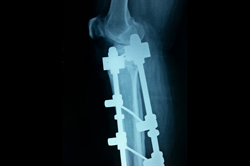

Elbow